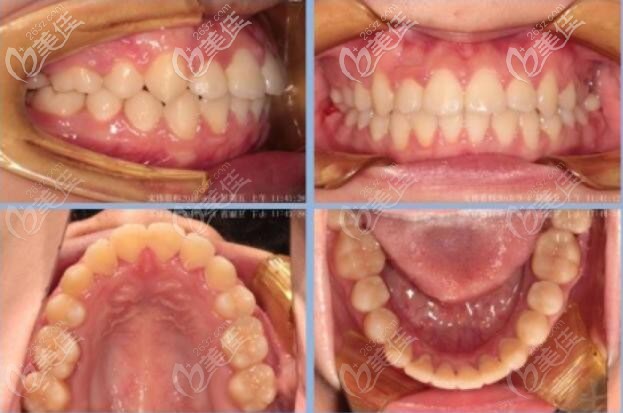

術(shù)后照片:

這次矯正整個(gè)過(guò)程也就兩年時(shí)間,當(dāng)然一般的成人矯正時(shí)間也是兩年。

綜合來(lái)講:這次矯正經(jīng)歷,不僅幫助顧客解決了凸面型的問(wèn)題還順便解決了智齒這個(gè)潛在隱患。一舉兩得,這次牙齒矯正可是說(shuō)是成功的。